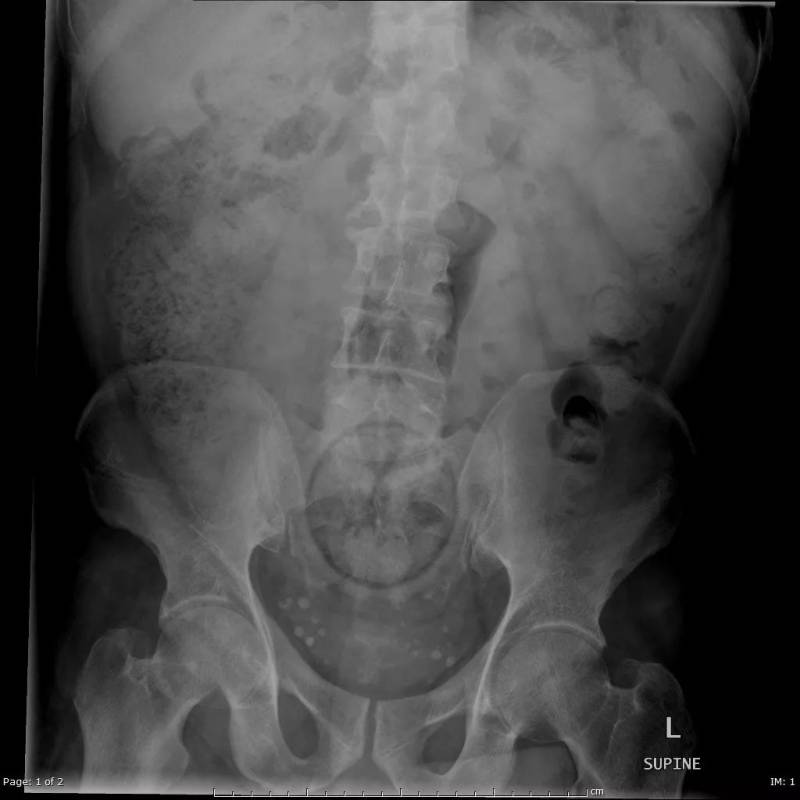

橙子

下腹部中央有一個圓形的異物,原來是患者自己塞進去的橙子。水果雖然是好東西,但不是這樣用法